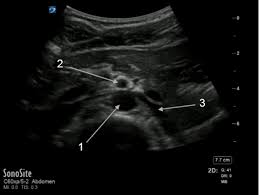

What is the long arrow  pointing at?

Hepatic artery

What is the red arrow pointing at?

SMA

What is the short arrow pointing at?

Splenic Artery

What is number 3?

LRV